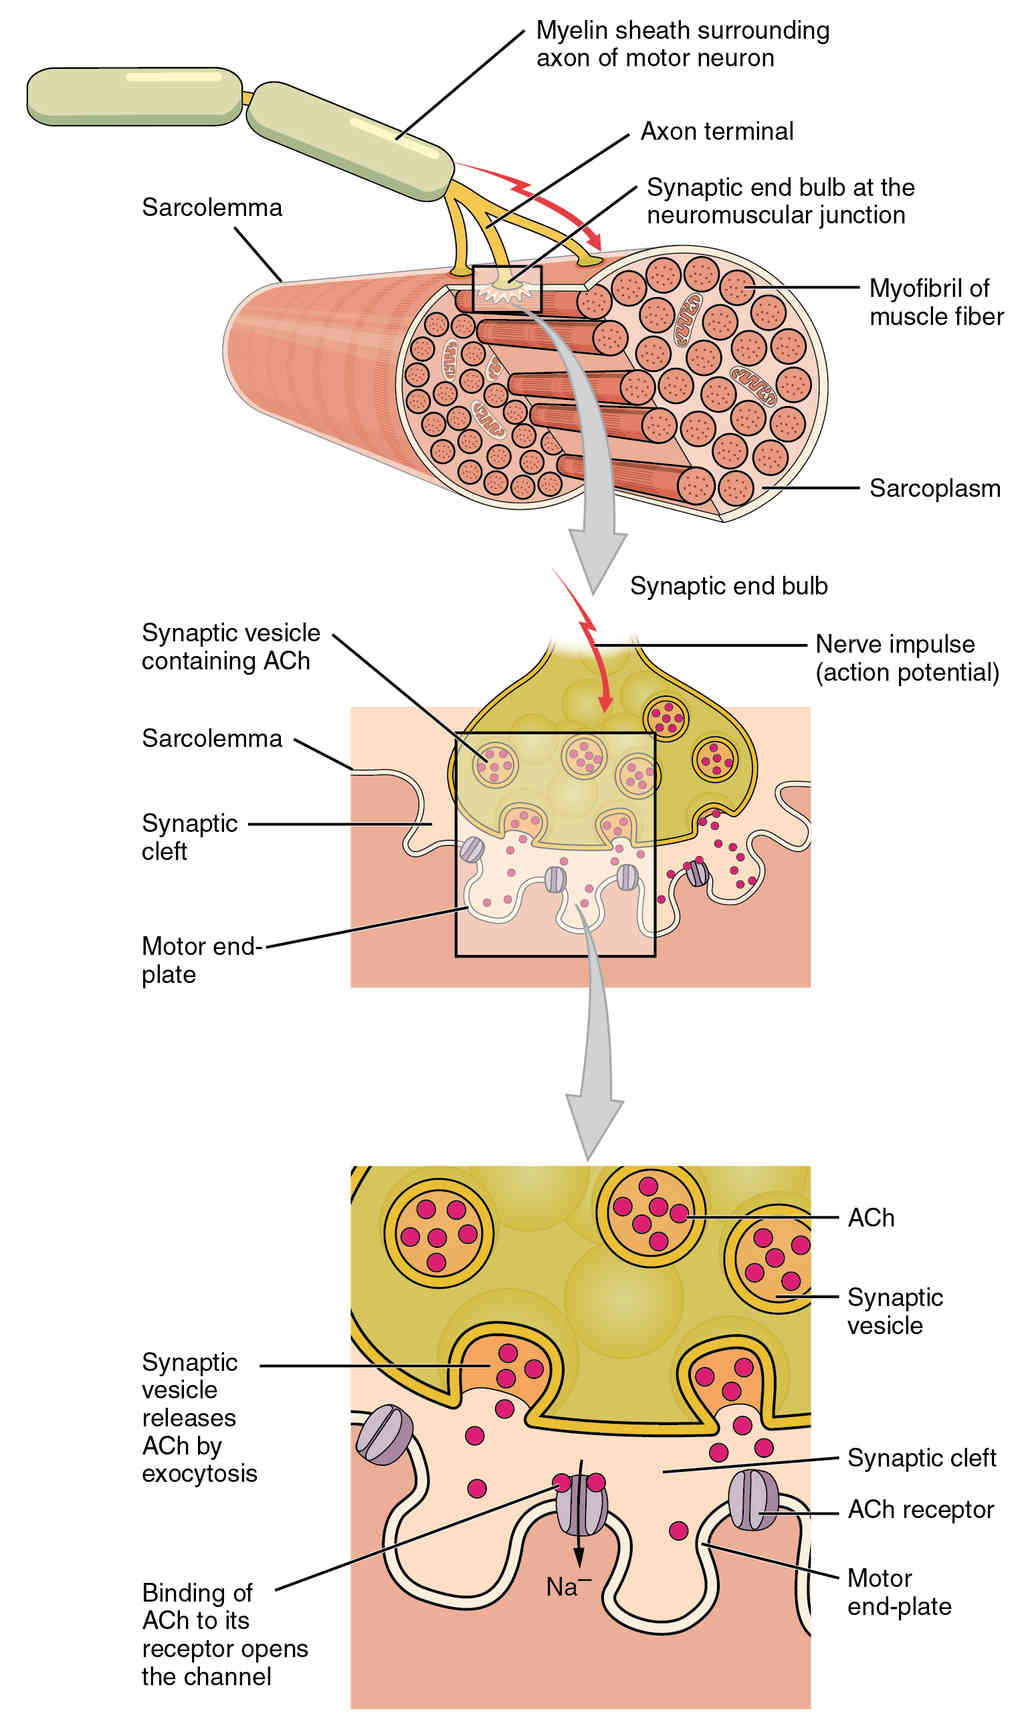

This page is under construction. For now, it is just a resource of the images found in the OpenStax Anatomy and Physiology Handbook. It wil slowly change into a revision tool. Each slide has a number. Use this to refer to the slide. When completed, it will have an unlabelled section, with labelled slides in parallel. On the unlabelled slides, write your answer and use the labelled slide to assess yourself. Keep track by also noting the number on each slide. Improvement at each attempt is important, more so than full marks on a first attempt.